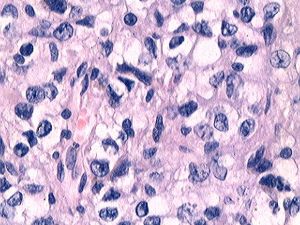

顱腦外傷、顳葉皮質支及顳葉深動脈閉塞、顳葉腫瘤時,均可導致顳葉損傷,出現相應的臨床症狀。